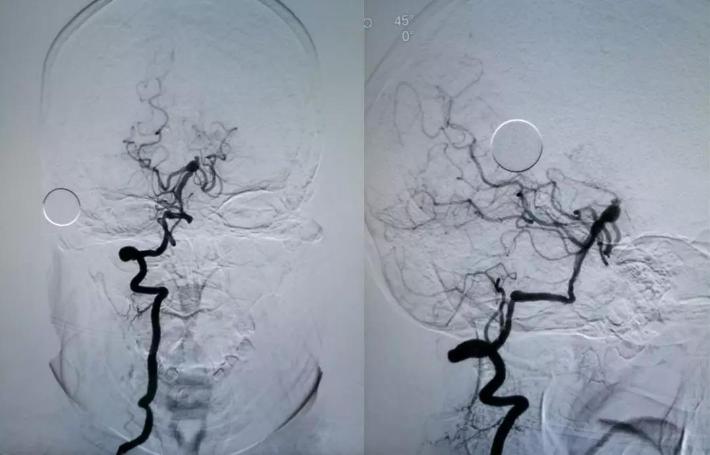

DSA

右侧颈内动脉虹吸段夹层动脉瘤,右侧大脑前动脉A1段纤细